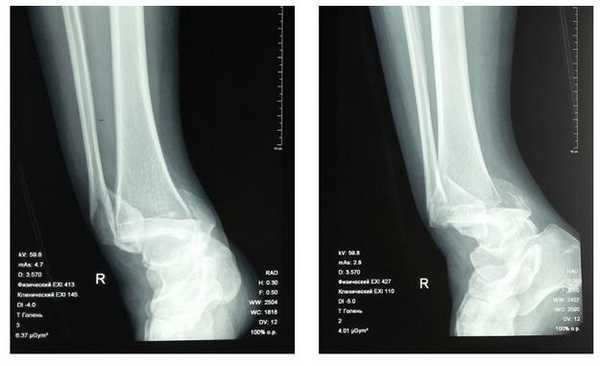

Пациентка Т. 80 лет. Травма за 3 недели до обращения, получила перелом обеих лодыжек правой голени со смещением, подвывихом стопы кнаружи. Обратилась в РТП, выполнена рентгенография, наложена гипсовая повязка. В связи с сохраняющимся выраженным отёком и болевым синдромом обратилась в клинику К+31.

На рентгенограммах в гипсе определяется значительный подвывих таранной кости кнаружи, консолидирующийся перелом нижней трети малоберцовой кости.

В день обращения пациентка послоностью обследована, проведено оперативное лечение, открытая репозиция, остеосинтез перелома нижней трети малоберцовой кости пластиной, внутренней лодыжки винтом, внутренняя лодыжка дополнительно фиксирована анкерным фиксатором.

На контрольных рентгенограммах после операции положение отломков, металлофиксаторов правильное, подвывих таранной кости устранён.